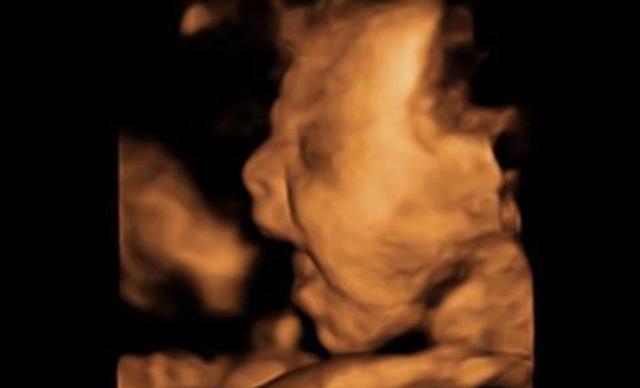

Vào tuần thai thứ 28, anh Stuart đã đưa chị Lucy đi siêu âm để kiểm tra sự phát triển của thai nhi. Qua siêu âm 4D, anh chị đã nhìn thấy hình ảnh con mình đang vẫy tay chào bố mẹ hết sức đáng yêu. Chị Lucy thậm chí còn cho rằng, em bé đã quay mặt ra nhìn về phía bố mẹ.

Cậu bé "lém lỉnh" ngay từ trong bụng mẹ với hình ảnh vẫy tay chào bố mẹ hết sức đáng yêu (Ảnh cắt từ clip)